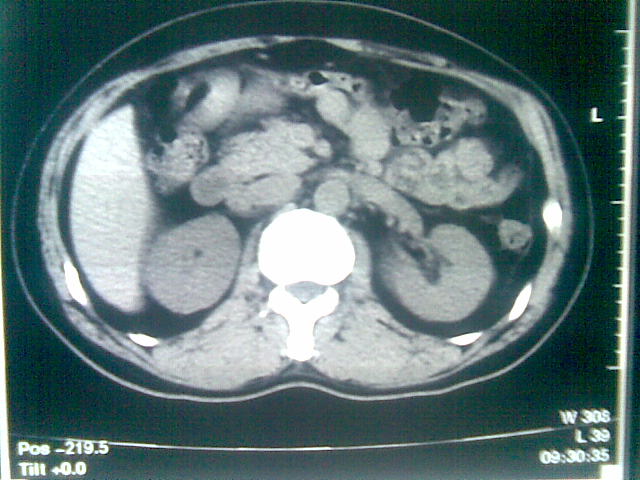

标题: CT23981:男,38岁阑尾炎术后透视胸腔积夜!做CT如下!积液包 [打印本页]

标题: CT23981:男,38岁阑尾炎术后透视胸腔积夜!做CT如下!积液包

可能与阑尾术后关系不太大,1.胸膜增厚粘连见少量气体。包裹脓气胸?左侧网膜囊脓肿?

少量积液部分粘连

左侧胸膜增厚、粘连+包裹液气胸。